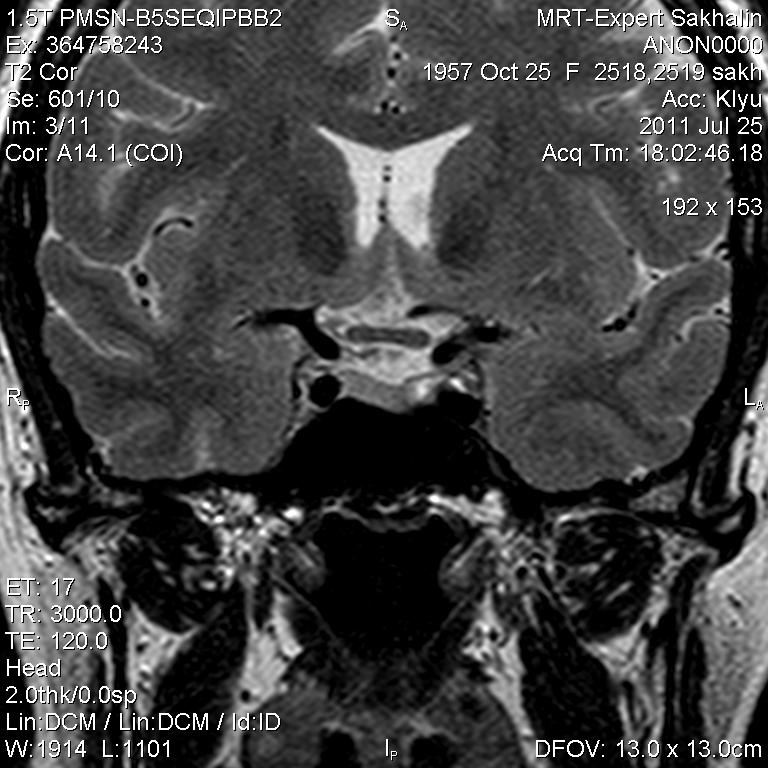

Женщина.6 лет назад выявлено образование левой доли нейрогипофиза.Пришла на контроль.

Постконтраст

Мне самой показался случай не совсем ясным, но динамик четко показывает участок с отставанием в контрастировании, воронка смещена вправо-о чем  думать бедному начинающему специалисту?